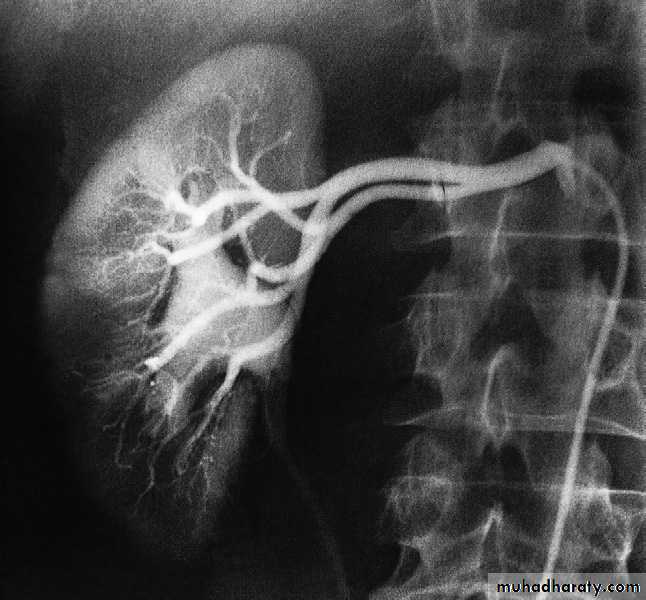

Renal arteriography

Renal arteriography is performed via a catheter introduced into the femoral artery by the Seldinger technique . Selective injection are made into one or both renal arteries . It is mainly used:- To confirm the CT or MRI findings of vascular anatomy prior to renal surgery.

-To confirm renal artery stenosis prior to percutaneous balloon angioplasty.